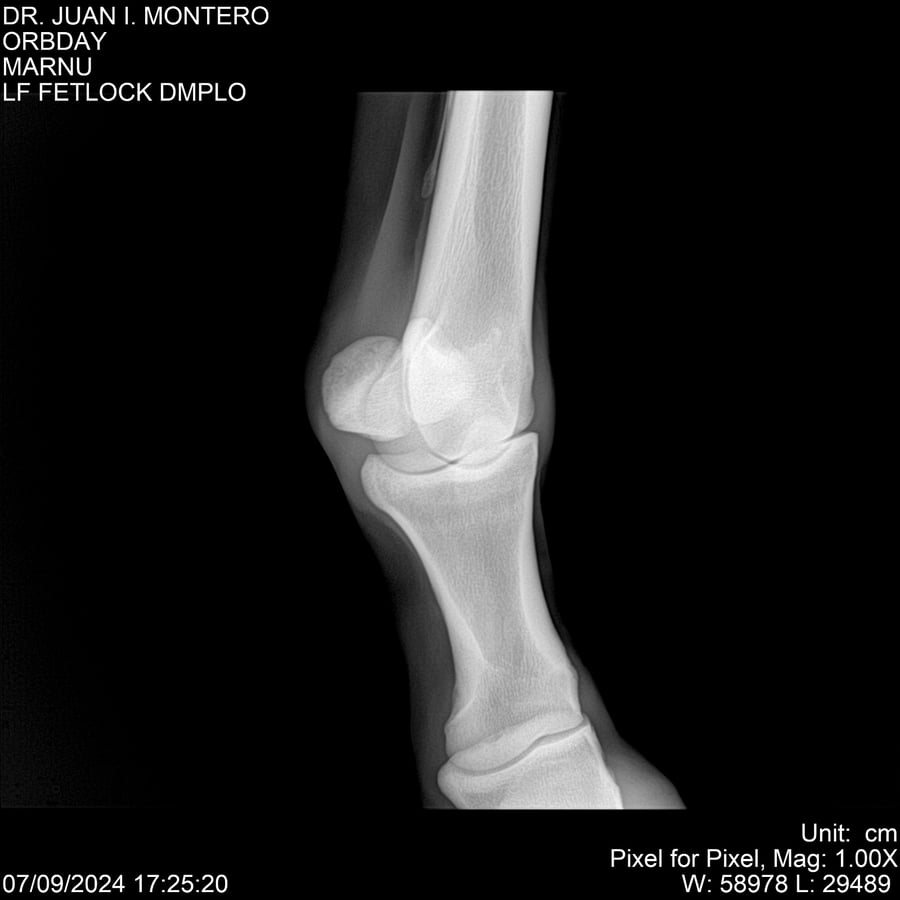

• Empresa: Abelenda N. R., Walter Hugo